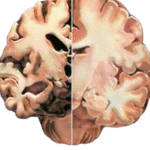

A livello Cerebrale l’immagine che segue parla da sola, a mostrare le conseguenze dell’abuso di sostanze stupefacenti. L’emisfero a sinistra è del cervello di una persona che fa uso di droghe: la corteccia si assottiglia, le sostanza bianca delle connessioni nervose si dirada, il cervello si atrofizza in maniera irreversibile dando il via al processo della demenza precoce, ma questa è un’altra storia.